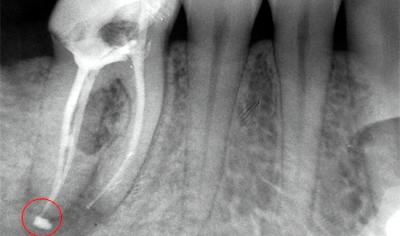

Выход пломбировочной пасты за апекс корня зуба

Апекс корня — его вершина. Иногда, при ошибках, допущенных стоматологом, пломбировочный материал выходит за пределы корня в область костей челюсти, вызывая воспаление мягких тканей.

Воспалительный процесс развивается из-за того, что пломбу — инородное тело организм пытается отторгнуть. Чтобы таких последствий не возникло, врач с помощью специальных приборов, измеряет длину канала.

Если зуб имеет несколько корней, то измеряется каждый канал. С помощью рентгена проверяется качество выполненной работы. Благодаря развитию медицины, приборы точно показывают, вышел ли пломбировочный материал за допустимые пределы. При обнаружении такого недочёта, врач должен снять пломбу и заново провести процедуру.